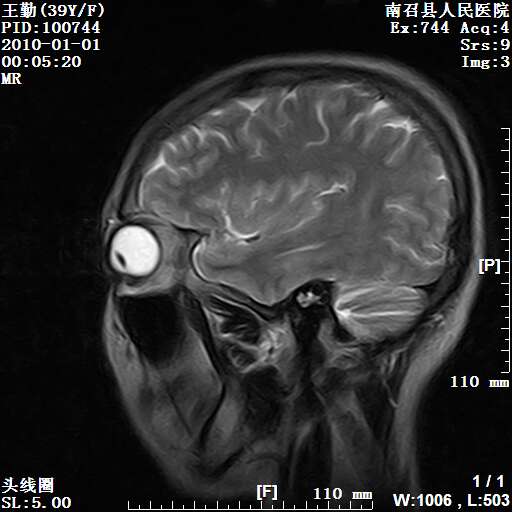

以下是引用随光逐影在2010-1-22 9:03:00的发言:[br]考虑左侧中颅窝(蝶骨翼区)脑膜瘤侵犯蝶骨翼并突入左侧眼眶。

以下是引用水过无痕在2010-1-22 14:55:00的发言:[br]一、定位:颅外占位;二、定性:恶性可能性大;三、组织来源:来源于左侧眼外直肌或其他部位;考虑为:横纹肌肉瘤>转移瘤>脑膜瘤.